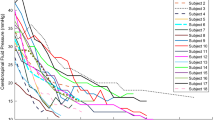

Cranio-Spinal Canal Compliance Distribution

A system analysis approach has been applied to estimate the cranio-spinal (CS) compliance distribution. A previously reported subject-specific lumped parameter model was employed to obtain the transfer function of the craniospinal system where the momentary difference between the arterial inflow and the venous outflow to and from the cranial vault is the input and the driving force for the cranio-spinal CSF pulsation, i.e., the output of the system [14]. A schematic representation of the compartmental model of the cranio-spinal system and an example of the MRI-derived waveform of blood and CSF flows demonstrating the input–output relationship between the blood and the CSF flow are shown in Fig. 1. The electrical circuit of the biomechanical analogous model includes the following lumped parameters: cranial and spinal compliance (C1 and C2 respectively), cranial and spinal CSF flow resistance (R1 and R2 respectively), and an inertia component (I2) to model the inertia-dominated CSF flow between the cranium and spinal canal [11]. The biomechanical characteristics of the CS system can be expressed by a transfer function, H(s), shown in Eq. 1, which is the ratio of the Laplace transforms of the output (CSF flow waveform) to the input (arterial minus venous flow waveform).

The ratio of the cranio and spinal canal compliance is then obtained by dividing the zero order coefficients in the numerator and denominator of the transfer function, as shown in Eq. 2.

Mean and SD values of total cerebral blood flow (TCBF), total internal jugular flow (TIJF), flows through dominant internal jugular veins (DIJF), nondominant internal jugular veins (NIJF), and total internal jugular flow (TIJF) normalized to total cerebral blood flow are summarized in Table 1. Venous drainage through the primary venous channels is significantly reduced in IIH patient compared with healthy subjects. This difference is further enhanced after normalization with total cerebral blood flow as demonstrated by the smaller p value (p value < 0.004). Example of a 3D MRV rendering of the extra-cranial venous vasculature from a control subject and from an IIH patient demonstrating the increased drainage through secondary channels in IIH is shown in Fig. 2. Means and SDs of morphological measures, CSF production rates and contribution to spinal canal compliance are summarized in Table 2. A trend toward slightly larger ventricular volumes in the IIH was observed. However, this trend was not statistically significant. No difference was found in CSF production rates between IIH and healthy. However, a larger but not significantly different variability in the CSF production was observed. In contrast to the morphological measures, spinal canal compliance contribution is significantly different in IIH and controls. A significantly smaller contribution to spinal canal compliance (0.6 vs. 0.75) was found in IIH (p = 0.026).

An MRI-based comprehensive characterization of the cerebral hemodynamics, venous drainage, cerebral ventricular morphology, and cranio-spinal compliance distribution was applied to homogeneous cohorts of pretreated female IIH subjects and an age- and BMI-similar group of healthy women. Several significant differences that further elucidate the pathophysiology of IIH have been identified. The most significant finding of this study is a contribution to lower spinal canal compliance in IIH. Mechanical compliance represents the ability of a compartment to accommodate an increase in volume without a large increase in pressure. A subject-specific assessment of the relative contribution of the spinal canal to the overall cranio-spinal compliance based on the relationship of the blood flow and cranio-spinal CSF flow reveals that spinal canal compliance buffering is significantly reduced in IIH.